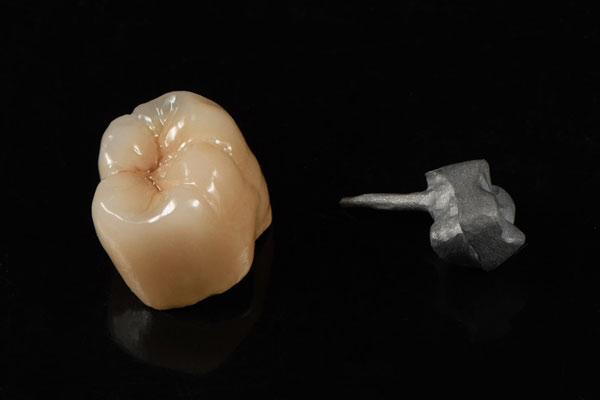

Dental Crown & Bridge is a permanent dental prosthesis. It is firmly fixed (attached) to patients’ prepared teeth, and will not be taken out of their mouths during the day and night. This kind of restoration is like patients’ natural teeth, offering excellent chewing and biting strength, remarkable oral hygiene, and superior aesthetics.

Crown & bridge category includes Onlays and inlays, Post and Core, Veneers, and Dental implants. It also consists of different materials like zirconia, E.max, composite resin, porcelain-fused-to-metal (PFM), full metal cast (FMC), and pure titanium. Those materials bring different effects.